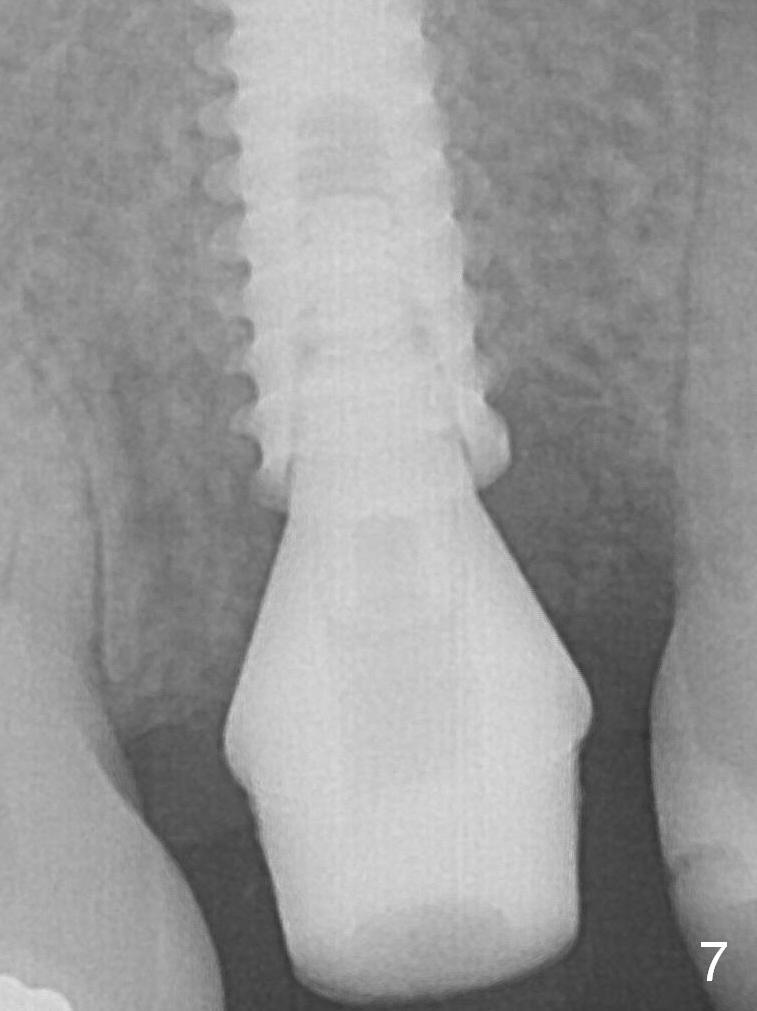

The implant was placed deep enough without thread exposure; now with apparently complete abutment seating (Fig.11). The similar complication may recur due to refusal to have implant at #19 (fear of nerve injury).